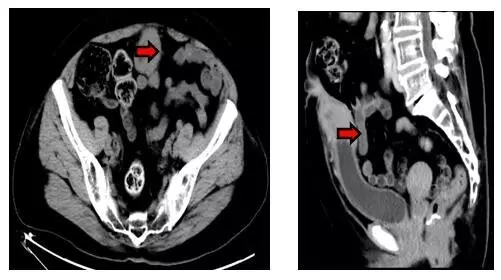

本例患者不是男性而是71歲女性,因“臍部溢液并下腹部紅腫硬塊”前來就診,之前也曾到過醫(yī)院但并未引起足夠的重視。家屬找到楊偉忠主任醫(yī)師后,經(jīng)仔細(xì)詢問病史并檢查病人,楊主任馬上診斷是臍尿管的慢性病變,并且高度懷疑腫瘤的可能性。立即給予下腹CT檢查報(bào)告為:“下腹部正中線區(qū)域臍-膀胱頂部之間軟組織腫塊影,性質(zhì)待定:臍尿管腫瘤?炎癥性病變?(見下圖)”。